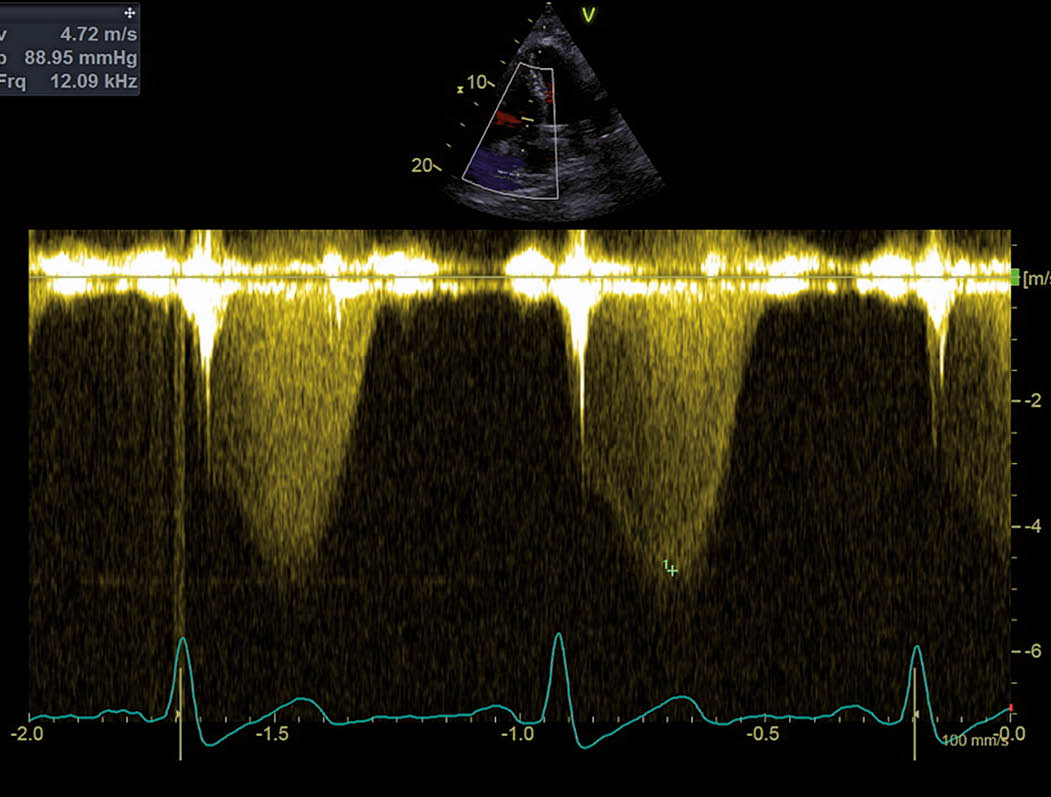

Abb. 1: RV-fokussierter apikaler Vierkammerblick Es zeigt sich ein exzentrisch hypertropher, dilatierter rechter Ventrikel. RV = rechter Ventrikel, LV = linker Ventrikel, RA = rechtes Atrium und LA = linkes Atrium.